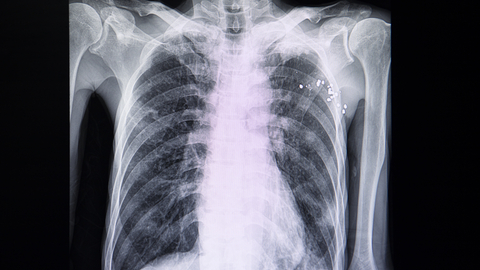

Some adults with severe respiratory illness, including women, those with public insurance, and people with fewer financial resources, may be less likely to receive an advanced form of life support known as extracorporeal membrane oxygenation (ECMO). A research team supported by the National Institutes of Health found that adults who received ECMO appeared to skew toward men, people with private health insurance, and those who came from areas with higher median incomes. ECMO helps patients with life-threatening illness or injury breathe by simulating the function of the heart and/or lungs, while giving those organs a chance to rest.

The study is published in the Annals of the American Thoracic Society. In ECMO, a machine pumps blood out of the body, sends it through devices that feed it oxygen, and then returns it to the body. It is typically a treatment of last resort and provided to patients who first receive mechanical ventilation, a standard type of breathing assistance used in critical care.

Researchers reviewed health insurance data from more than 2 million adults with severe respiratory illness between 2016 and 2019, using the Nationwide Readmissions Database. All patients first received mechanical ventilation, which in this case was defined as having a breathing tube inserted into the airways to help their bodies receive enough oxygen. Supplemental oxygen can also be provided through a face mask or breathing tubes inserted into the nostrils, but this review only looked at advanced breathing assistance. Among adults who received mechanical ventilation, 18,725 also received ECMO. After conducting multiple analyses, the researchers found that men received ECMO more often than women, even if they had the same type of insurance and income level. Men accounted for 64% of patients receiving ECMO compared to 36% of women. In addition, men made up 55% of those who just received mechanical ventilation, compared to 45% of women.